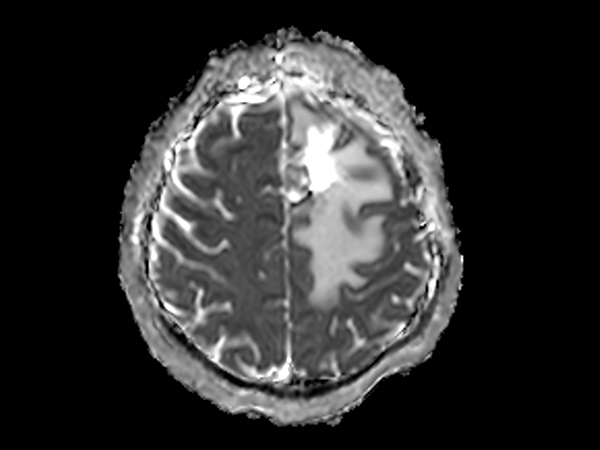

SmartSpeed Precise imaging for brain with glioblastoma

Kyushu University Hospital Japan